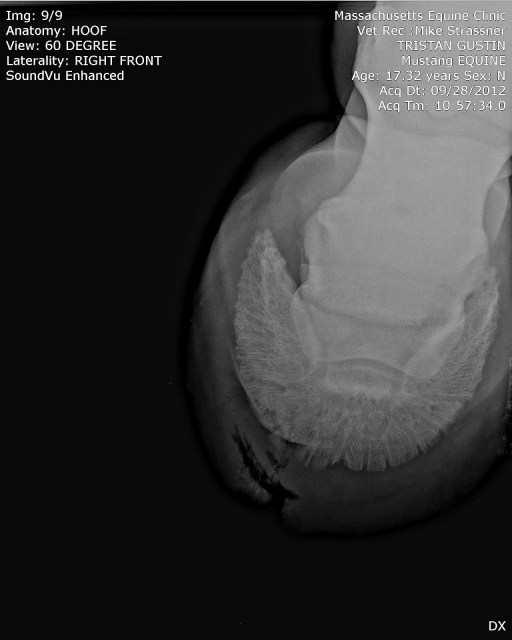

| And now, with holes. You can see the top hole, and the bottom hole, and the track all the way down to the sole. |

| And the top-down view of the hole, showing its width as well. Eek. |